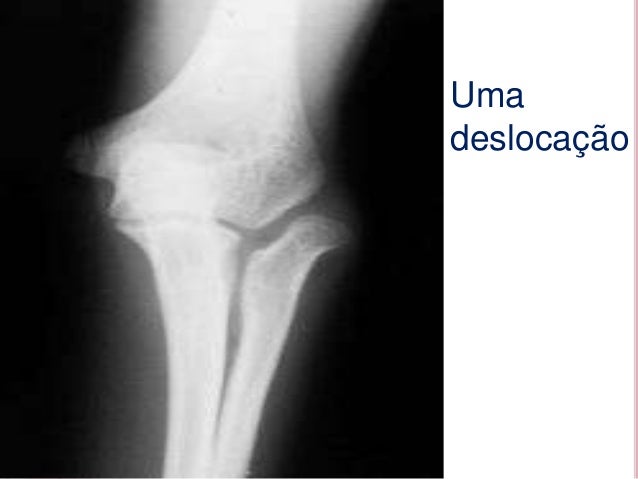

1. 1. OS OSSOS DO CORPOHUMANO

3. 3. Crânio, Maxilar, Ma ndíbula, Clavícula, 1- Identificar os Escápula, Esterno, Costelas, Coluna, Úossos mero, Rádio, Ílio, S acro, Púbis, Fémur, Paleta (rótula), Tíbia, Tarso , Metatarso, Falang es do pé, Corpo, Metacar po, Falanges das mãos, …

11. 11. Umadeslocação